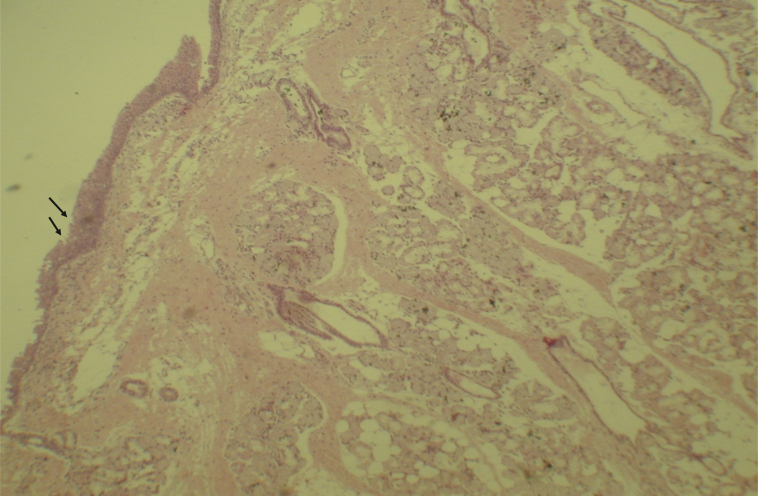

Histological evaluation of sinus mucosa showed various degrees of inflammation, characterized from intense infiltration of inflammatory cells (Fig. 2), epithelial alterations (Fig. 3), neovascularization, glandular destruction and connective-fibrous proliferation to mucosa practically normal (Fig. 4). Such variations were present in both treatment groups (Table 2).

Mucosa of the maxillary sinus showing areas of erosion in the epithelium (arrows) and inflammatory cells. Optical microscopy, HE staining, 100×.

Figure 4.

Mucosa of the maxillary sinus showing normal epithelium, without inflammatory process. Optical microscopy, HE staining, 100×.